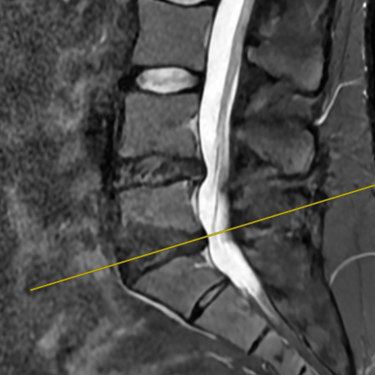

La discopatía degenerativa lumbar es una de las principales causas de dolor lumbar crónico. Se caracteriza por la pérdida de altura discal, deshidratación y cambios en las superficies vertebrales adyacentes. En la resonancia magnética (RMN) se identifican los cambios Modic, que reflejan alteraciones inflamatorias y degenerativas en el hueso subcondral: tipo I (edema), tipo II (grasa) y tipo III (esclerosis). Estos hallazgos permiten correlacionar el dolor lumbar con la patología discal y orientar un tratamiento personalizado. La RMN es, por tanto, una herramienta esencial para el diagnóstico preciso y la planificación terapéutica en pacientes con esta condición.